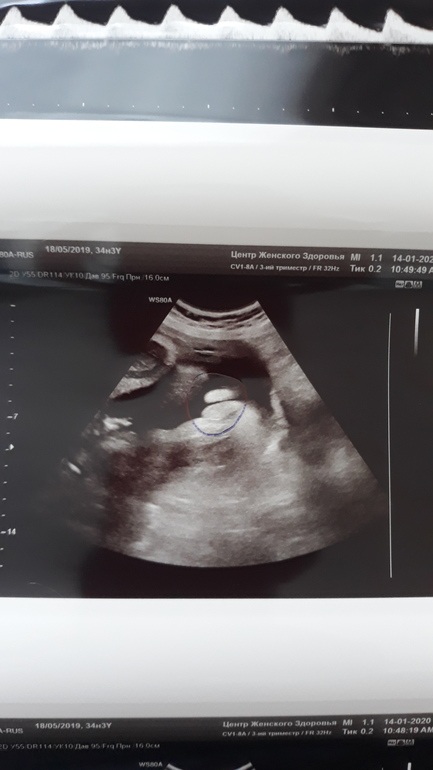

На 3 скрининге в ЖК вредная врач пол не сказала, т.к Она пол не смотрит ( ее слова), но обнаружила у нас ППК, нарушение кровотока, вообщем врач назначила лечение и УЗИ контроль через 2 недели. Приехала сегодня, лежу, она мне говорит: ну, пол знаете наверно? Я: в 15 недель предположили мальчика, но не точно.

Она: нет, у вас девочка, без вариантов, 100 %. Начала показывать и объяснять, я же кроме пистолетов своих мальчишек😄 на фото УЗИ не видела. И даже обвела ручкой.

Наше кофейное зернышко🥰🥰🥰😊